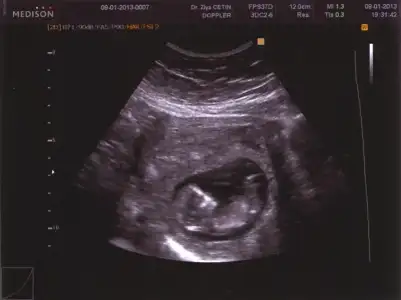

fazla durmadi daha oncede demistim cok sacma ultrasona bakti osekil nasil gorecekse cocun kafasi yukaridaymis donmedi oyuzden goremiyom dedi.turkiyedeki dr. gittigimde videoya cekmistim 12.13 haftalikdi ozamanlar buraya yukllemek istiyorumda konustugumuz seslerde var oyuzden koyamiyom hayirlisi allahtan canim ..

demem o ki 12 13 haftalikken bidaha koy sen ama maaasallah bebegin cok iri gozukuyor :)